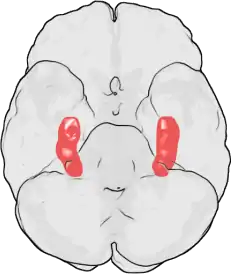

The effects of stress on memory include interference with a person's capacity to encode memory and the ability to retrieve information.[1][2] Stimuli, like stress, improved memory when it was related to learning the subject.[3] During times of stress, the body reacts by secreting stress hormones into the bloodstream. Stress can cause acute and chronic changes in certain brain areas which can cause long-term damage.[4] Over-secretion of stress hormones most frequently impairs long-term delayed recall memory, but can enhance short-term, immediate recall memory. This enhancement is particularly relative in emotional memory. In particular, the hippocampus, prefrontal cortex and the amygdala are affected.[5][6] One class of stress hormone responsible for negatively affecting long-term, delayed recall memory is the glucocorticoids (GCs), the most notable of which is cortisol.[1][6][7] Glucocorticoids facilitate and impair the actions of stress in the brain memory process.[8] Cortisol is a known biomarker for stress.[9] Under normal circumstances, the hippocampus regulates the production of cortisol through negative feedback because it has many receptors that are sensitive to these stress hormones. However, an excess of cortisol can impair the ability of the hippocampus to both encode and recall memories.[2] These stress hormones are also hindering the hippocampus from receiving enough energy by diverting glucose levels to surrounding muscles.[2]

PTSD can affect several parts of the brain such as the amygdala, hippocampus, and the prefrontal cortex. The amygdala controls our memory and emotional processing; the hippocampus helps with organizing, storing and memory forming. Hippocampus is the most sensitive area to stress.[59] The prefrontal cortex helps with our expression and personality and helps regulate complex cognitive and our behavior functions.